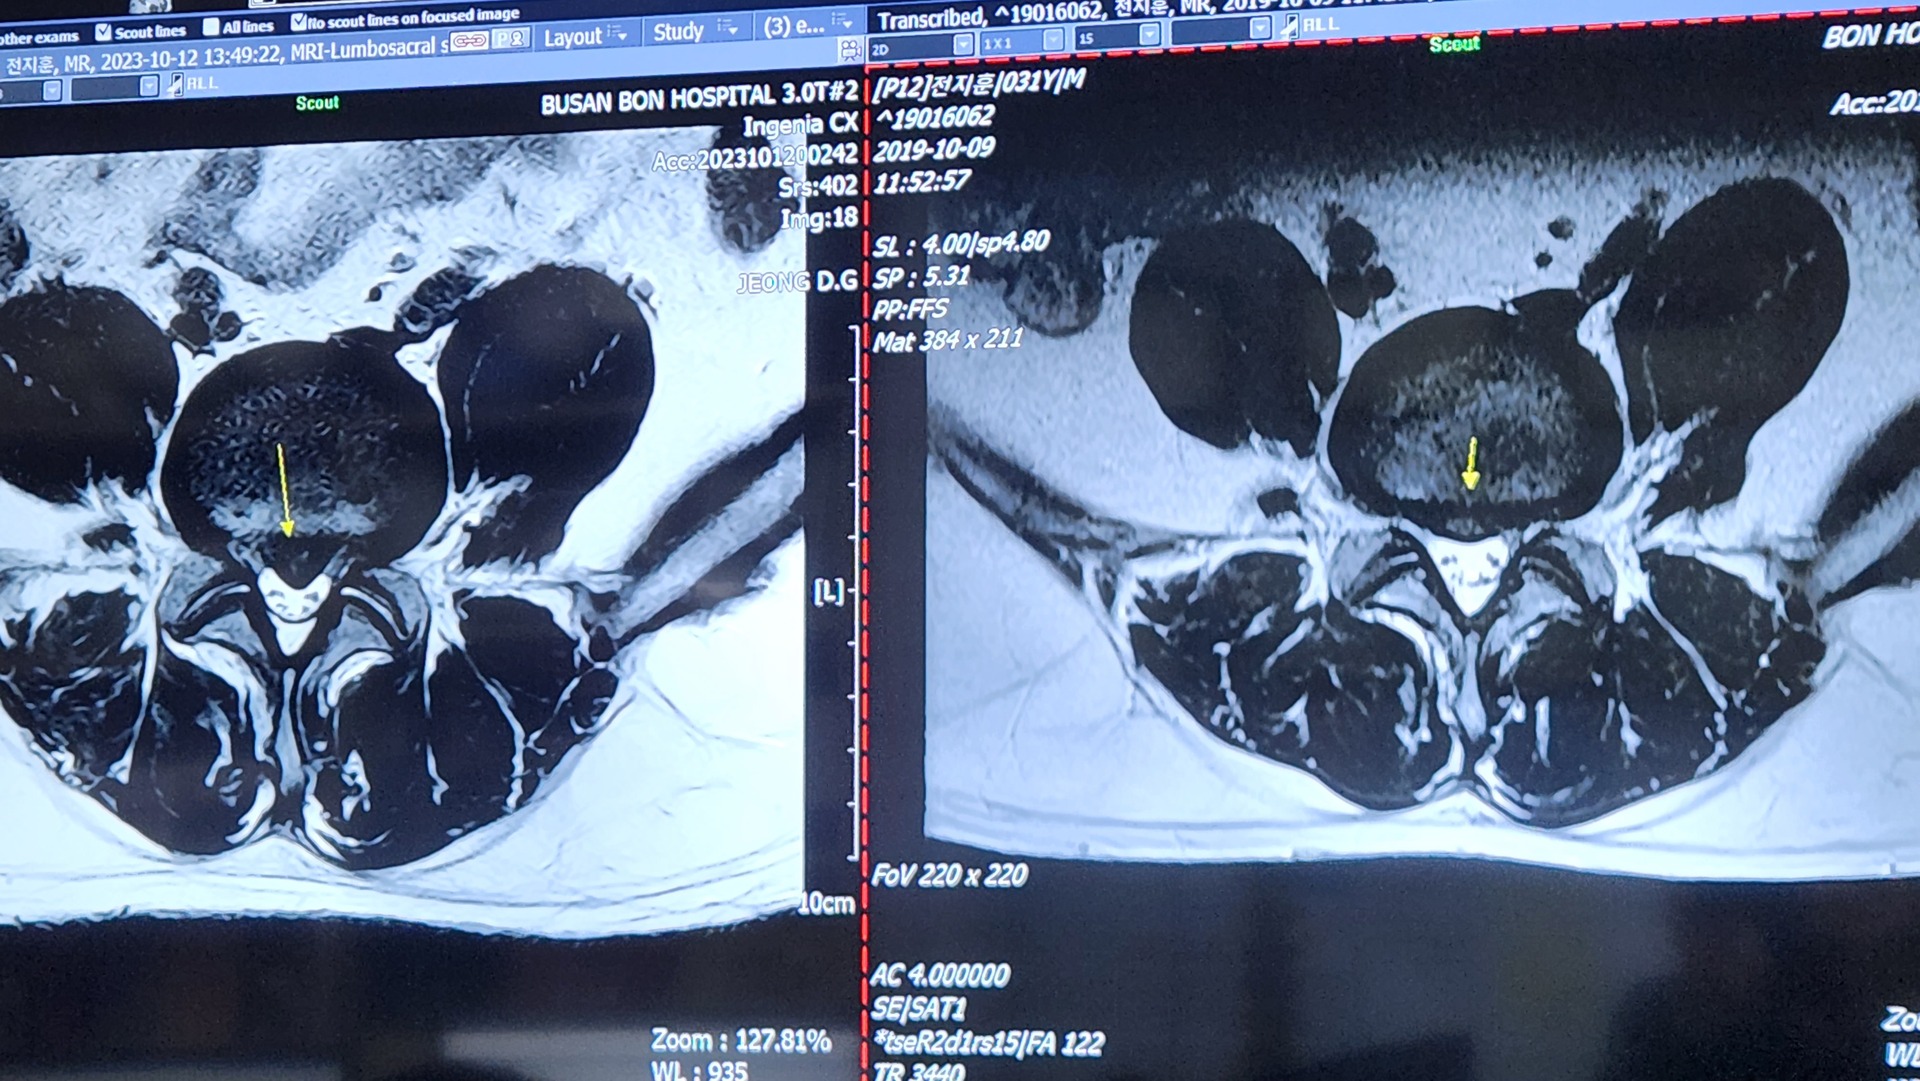

홈진료상담 및 문의 진료상담 및 문의 아들 허리 디스크 추간판탈출증 작성자 강혜정 (엄마) 작성일 2023-10-13 02:11 조회 247 아들88년생입니다. 허리 상태 이고요? 병원에서 수술해야된다고 하는데 치료해서 완쾌 될수있을까요? 가능하다면 방문하고 싶은데요? 좋아요 0 싫어요 0 인쇄 « 누구를 위한것인가 ccc » 목록보기 답글쓰기 글수정 글삭제 Powered by KBoard